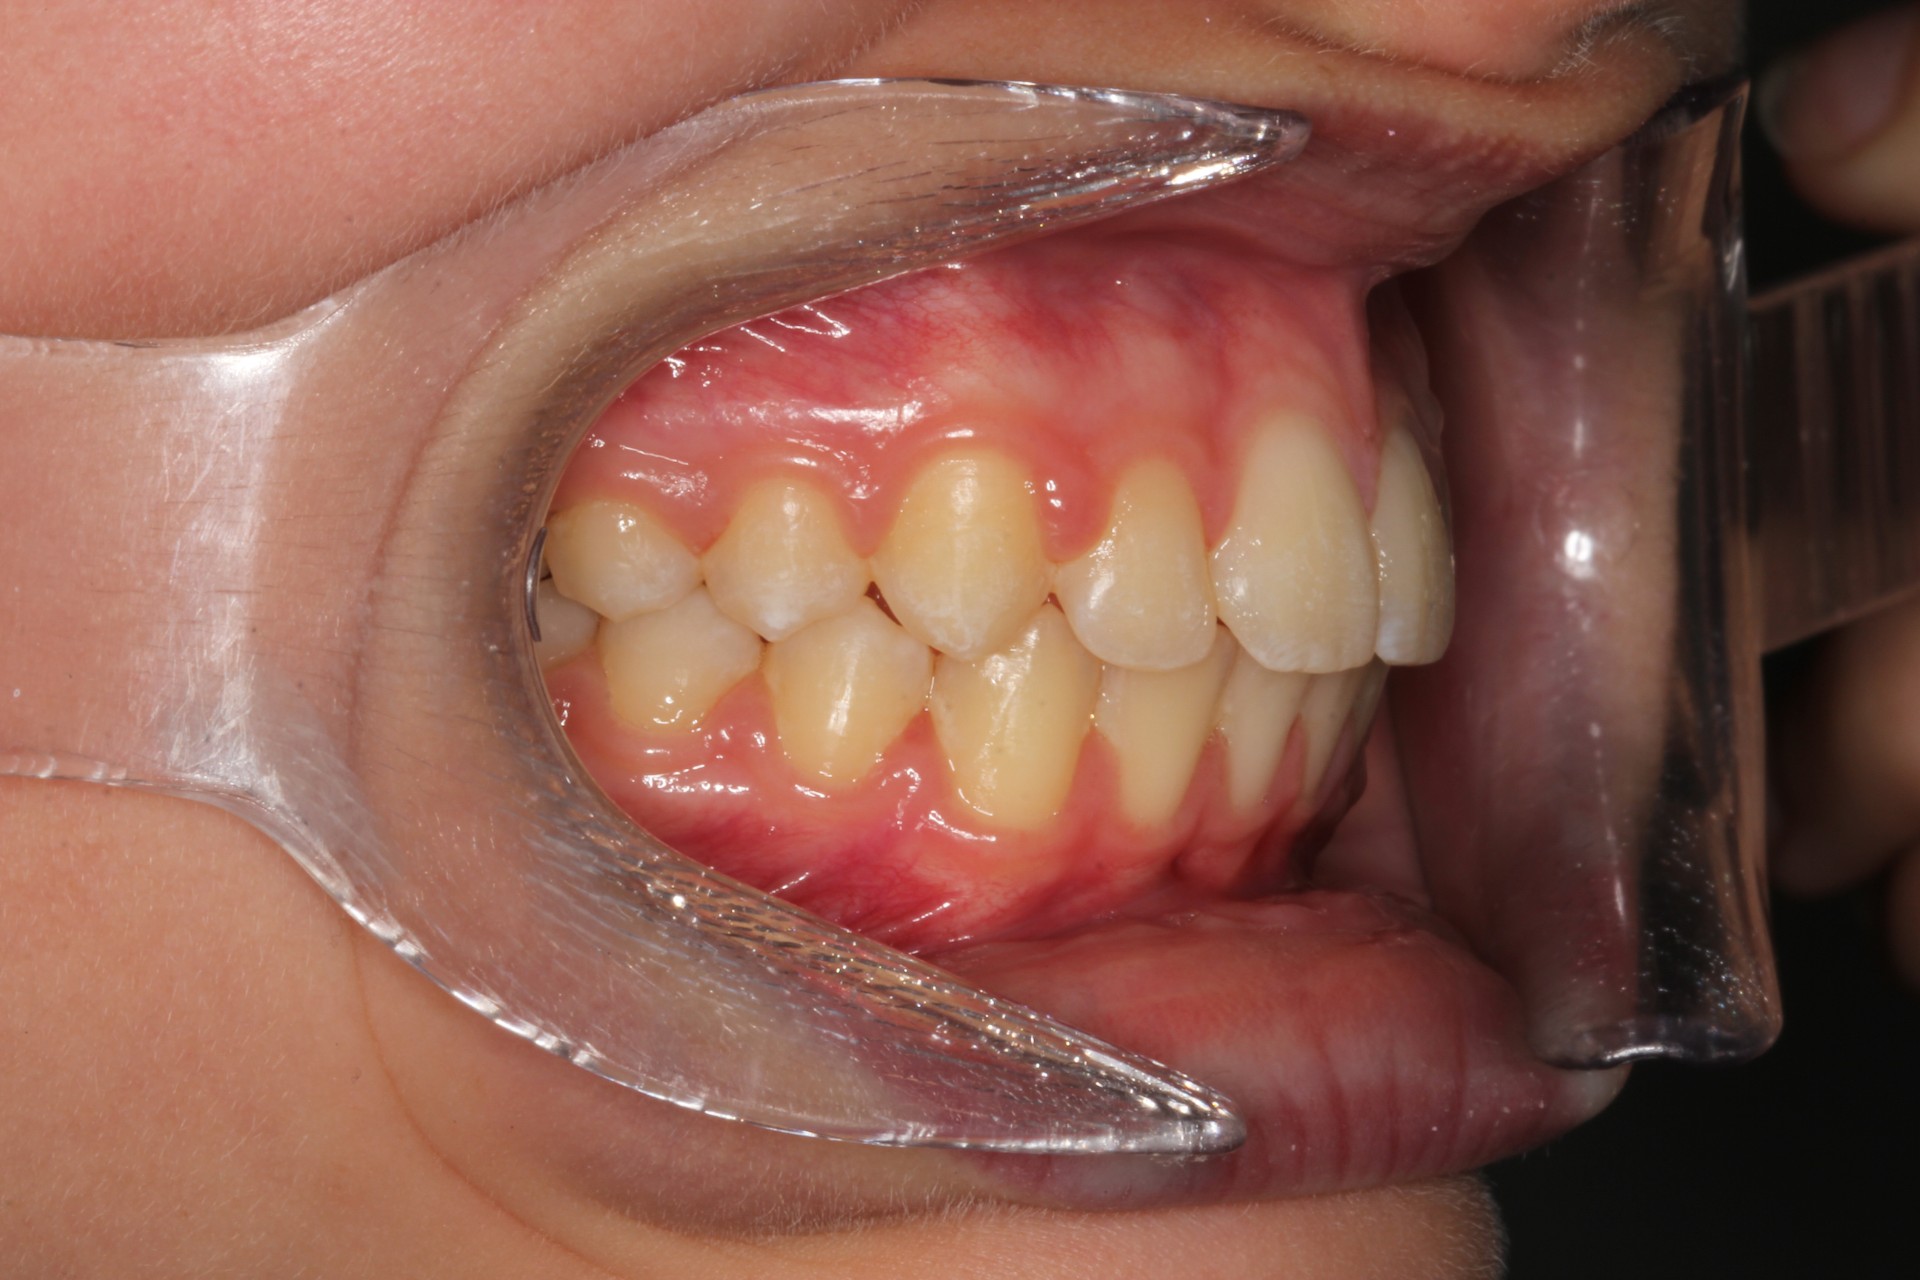

Protruding front teeth – Child case